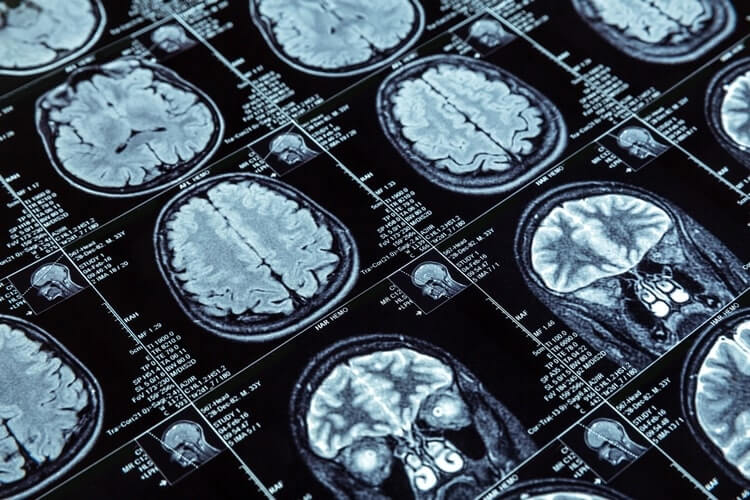

Největším problémem při diagnostice nejsou špatné nástroje a špatná kritéria, ale nevhodné užití jinak velmi dobrých nástrojů, například aplikace McDonaldových kritérií u nemocných s atypickými příznaky, bez objektivních klinických známek RS. Problém činí také nadhodnocení nálezu na magnetické rezonanci (MRI). Co se jeví jako RS, může být totiž ve skutečnosti léze vaskulárního původu či jiný zánět.

V rámci toho, že má pacient jasné klinické příznaky, může docházet k nadhodnocení výsledků pomocných metod. Pro RS jsou určující léze na MRI o velikosti minimálně 3 mm v podélné ose; jejich nejčastější lokalizace je kolmo na corpus callosum, v tomto případě už obvykle nemá smysl diagnózu RS zpochybňovat. Ukazuje se však, že například periventrikulární léze lze najít až u 60 % populace starší 60 let, proto některé studie doporučují minimální velikost léze pro diagnostiku RS v tomto věku upravit až na 6 mm.

Ložiska poškození CNS se pro prokázání DIS musejí nacházet alespoň ve dvou ze čtyř typických lokalizací – v oblasti periventrikulární, kortikální, juxtakortikální a infratentoriální (míšní) – a započítávají se i v případě, že jsou asymptomatická. Při zaměření na časový vývoj RS, tedy DIT, je třeba se dívat na současnou přítomnost Gd enhancujících a negativních lézí. Nutné je naopak dávat pozor na určování diagnózy čistě pouze podle výskytu nových T2W lézí, které nebyly na starší MRI, protože opět může jít o něco jiného, například vaskulární defekt.